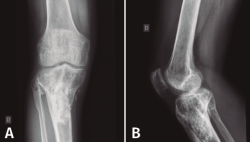

Figura 5. Radiografías de frente y de perfil del extremo proximal de la tibia donde se objetiva la cavidad en la tibia con presencia de material granulado en su interior.

En el estudio radiológico (Figura 5) se objetiva imagen cavitaria en el extremo proximal de la tibia con presencia de material granulado del injerto realizado.